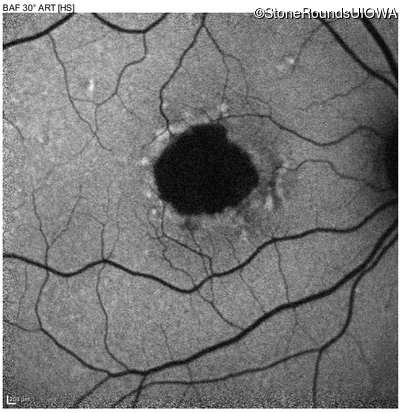

Pattern Dystrophy (IIC)

Age at visit: 51 years

This 51 year old woman first noticed some metamorphopsia in her left eye in her early 30's.

Pattern Dystrophy PRPH2 IVS2+3 A>T   AD